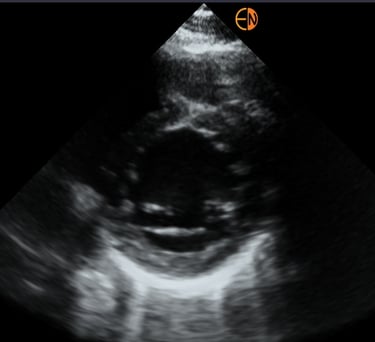

POCUS Cardíaco básico: Principais janelas cardíacas, avaliação da função sistólica dos ventrículos, avaliação do choque circulatório.